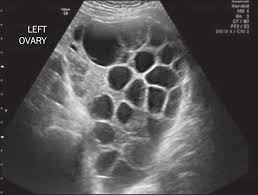

Ultrasound remains the radiological investigation of choice for initial.

The latter four entities are referred to as gestational trophoblastic neoplasia GTN. A common characteristic of all gestational trophoblastic disease is an abnormal proliferation of trophoblast but different components predominate in different tumors. Ultrasound remains the radiological investigation of choice for initial. Gestational trophoblastic neoplasia GTN encompasses a broad spectrum of placental lesions from the pre-malignant hydatidiform mole complete and partial through to the malignant invasive mole choriocarcinoma and rare placental site trophoblastic tumour PSTT. The latter four entities are referred to as gestational trophoblastic neoplasia GTN. There are several histologically distinct types of GTD that range from premalignant complete and partial hydatidiform moles HMs to malignant diseases also known as gestational trophoblastic. Ultrasound in the Diagnosis and Management of GTN Gestational trophoblastic neoplasia GTN includes invasive mole choriocarcinoma PSTT and ETT. Because it is an unusual and serious disease that affects women of reproductive age as well as because its appropriate treatment results in high cure rates it is crucial that radiologists be familiar with gestational trophoblastic disease in order to facilitate its early diagnosis and to ensure appropriate follow-up imaging. Gestational trophoblastic disease GTD is a spectrum of both benign and malignant gestational tumors including hydatidiform mole complete and partial invasive mole Choriocarcinoma placental site trophoblastic tumor and epithelioid trophoblastic tumor.

Gestational trophoblastic disease GTD encompasses a heterogeneous group of lesions including hydatidiform mole invasive mole choriocarcinoma and placental site trophoblastic tumor Mazur and Kurman 1994. The term gestational trophoblastic disease GTD encompasses a spectrum of tumors with a wide range of biologic behavior and potential for distant metastases. Gestational trophoblastic disease GTD is a term used for a group of pregnancy-related tumours. GTD refers to both the benign and malignant entities in the spectrum and includes hydatidiform mole complete and partial invasive mole choriocarcinoma placental site trophoblastic tumor PSTT and epithelioid trophoblastic tumor ETT. There are several histologically distinct types of GTD that range from premalignant complete and partial hydatidiform moles HMs to malignant diseases also known as gestational trophoblastic. Ultrasound in the Diagnosis and Management of GTN Gestational trophoblastic neoplasia GTN includes invasive mole choriocarcinoma PSTT and ETT. GTD refers to both the benign and malignant entities in the spectrum and includes hydatidiform mole complete and partial invasive mole choriocarcinoma placental.